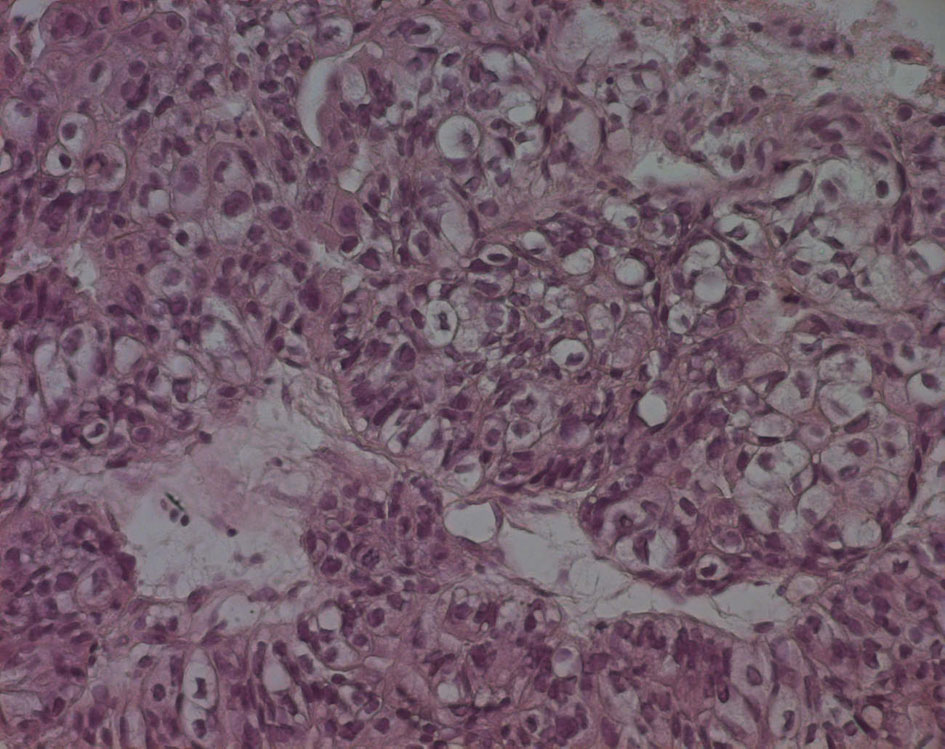

The pathological examination showed large and medium tumor cells with rounded nucleus and transparent cytoplasm, papillary and glandular structures were observed, and a normal seminal vesicle and prostate tissue were also found. This shows a poorly differentiated adenocarcinoma, but its origin was not yet clear (Fig. 4, 5).

![]() Click for large image | Figure 5. Echo-guided transrectal biopsy (high magnification). Large and medium tumor cells with rounded nucleus and transparent cytoplasm, papillary and glandular structures can be also found. |